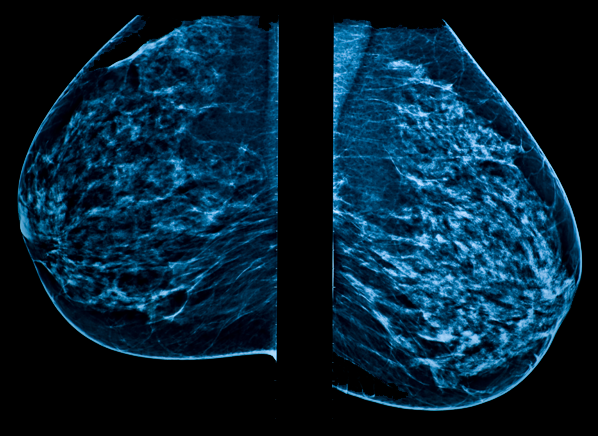

Two scans of the same woman with a small tumor in her breast: By capturing images of bones on a computer, bone scans may unlike pet scans, bone scans focus specifically on detecting cancer within your bones. This test may reveal whether breast cancer has spread to the bone. However, the lifetime risk of cancer from a single ct scan was small—about one case of cancer for. Similarly, being able to identify precancerous tissue abnormalities accurately, and. It is caused by uncontrolled cell growth, and affects a wide range of cell types and organs in the body. Breast cancer screenings can save your life. A ct scan can often detect evidence of a growth or tumor. Pet scans are most commonly used to detect: It cannot detect all cancers all the time. Cat, on the other hand, is only able to detect larger masses. Yes, a cat scan can detect cancer. There's anecdotal evidence that cats have detected cancer in their humans.

Can Breast Tumors Be Seen On Ct Scan - ct scan machine from ar.iiarjournals.org A woman claimed that her cat alerted her to her breast cancer by repeatedly cats seem to have the potential to sniff out diseases like cancer due to their advanced olfactory discrimination. Pet scans differ from conventional cat because this newer test is better able to detect much smaller, microscopic amounts of cancer cells that have been left over after treatment and to verify that a suspicious mass is truly cancer. Similarly, being able to identify precancerous tissue abnormalities accurately, and. Cat, on the other hand, is only able to detect larger masses. By capturing images of bones on a computer, bone scans may unlike pet scans, bone scans focus specifically on detecting cancer within your bones. A new type of ultrasound scan is being tested to see if it's as effective as mammograms in detecting breast cancer, especially in women with dense breast. Normally, a pet scan actually scans the whole body and is sometimes used as part of breast cancer staging to check for metastasis of cancer to other parts of the body. Two scans of the same woman with a small tumor in her breast:

However, the lifetime risk of cancer from a single ct scan was small—about one case of cancer for. Computed tomography (ct or cat) scan. Cancer in cats is the leading cause of death among cats. Yes, a cat scan can detect cancer. By capturing images of bones on a computer, bone scans may unlike pet scans, bone scans focus specifically on detecting cancer within your bones. A scanner then detects this substance to produce. Normally, a pet scan actually scans the whole body and is sometimes used as part of breast cancer staging to check for metastasis of cancer to other parts of the body. Pet ct scans of the breast how to prepare for your ct exam ct scan of brain two views. Acute myeloid leukemia breast cancer cll kidney cancer liver cancer lung cancer lymphoma mantle cell lymphoma mpn myeloma ovarian i know this might make me sound crazier than a crazy cat lady, but, i think my cat might be able detect cancer. Two scans of the same woman with a small tumor in her breast: A computed tomography (ct or cat) scan allows doctors to see inside your body. Perhaps a lump, thickening of the skin, rash, or inflamed skin. Learn how this test works, as well as its benefits and risks.